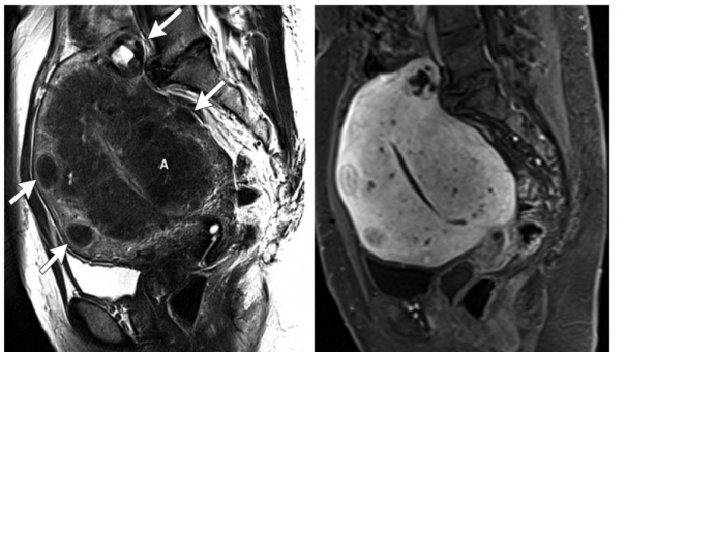

Paciente 31 anos com dismenorréia progressiva desde os primeiros ciclos, no momento refere dismenorréia incapacitante. Fez USG que evidenciou útero de dimensões normais, com imagem cística anexial com conteúdo espesso.

Kissing ovary, endometriose, Focos de sangramento no parenquima ovariano